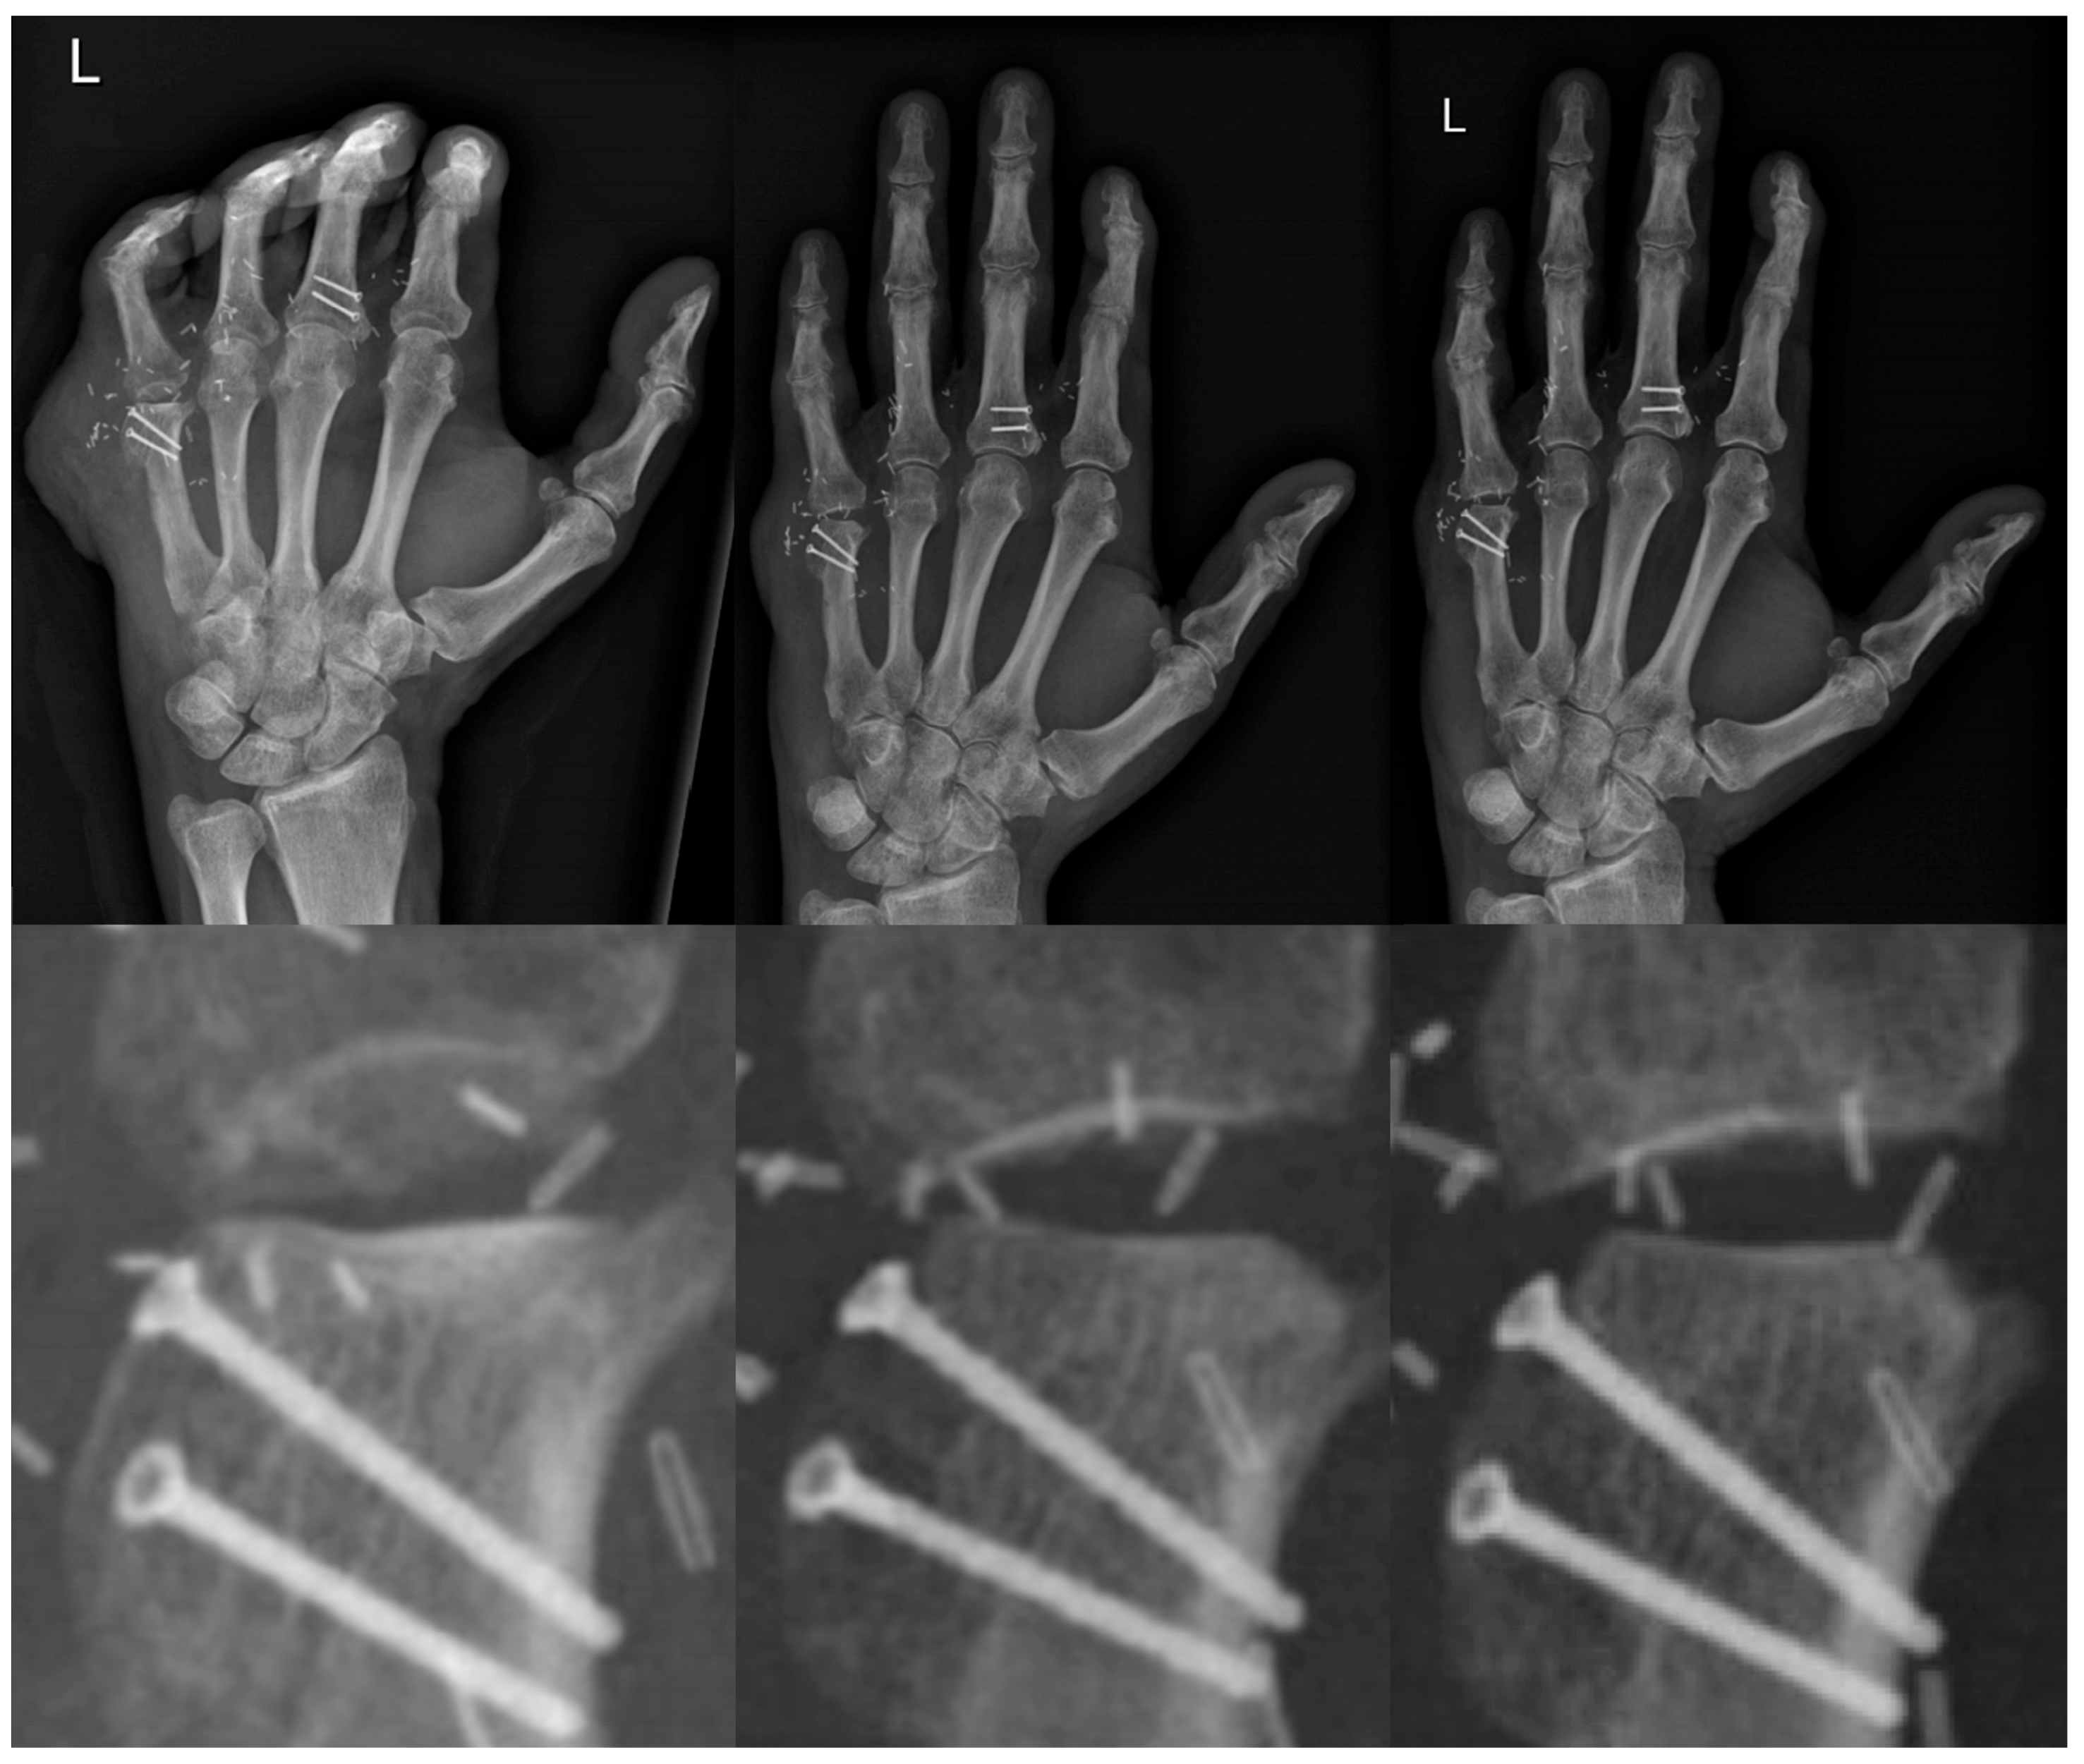

2. Case Report